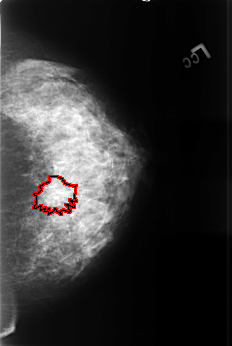

FILE: B_3390_1.LEFT_CC.OVERLAY

TOTAL_ABNORMALITIES 1

ABNORMALITY 1

LESION_TYPE MASS SHAPE ARCHITECTURAL_DISTORTION MARGINS SPICULATED

ASSESSMENT 4

SUBTLETY 3

PATHOLOGY MALIGNANT

TOTAL_OUTLINES 1

BOUNDARY